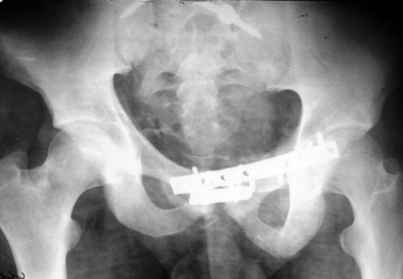

Застарелый перелом таза - результат

Уважаемые коллеги! 27 июля 2006г. представлял на форум больного со сложным застарелым переломом таза. Сейчас провели контрольное обследование.

Результат представляю в картинках.

Фиксация сзади выполнена системой "Силует" фирмы "Зиммер", предназначенной для транспедикулярной стабилизации позвоночника. Юрий Алексеевич Булахтин

Думаю. что если расспросить более детально, то жалобы все же обнаружатся. Pohlemann и сотоварищи не получили ни одного отличного функционального результата при резидуальном смещении в задних отделах более 10 мм (здесь явно больше). Действительно на функциональных фото все выглядит неплохо, поздравляю.